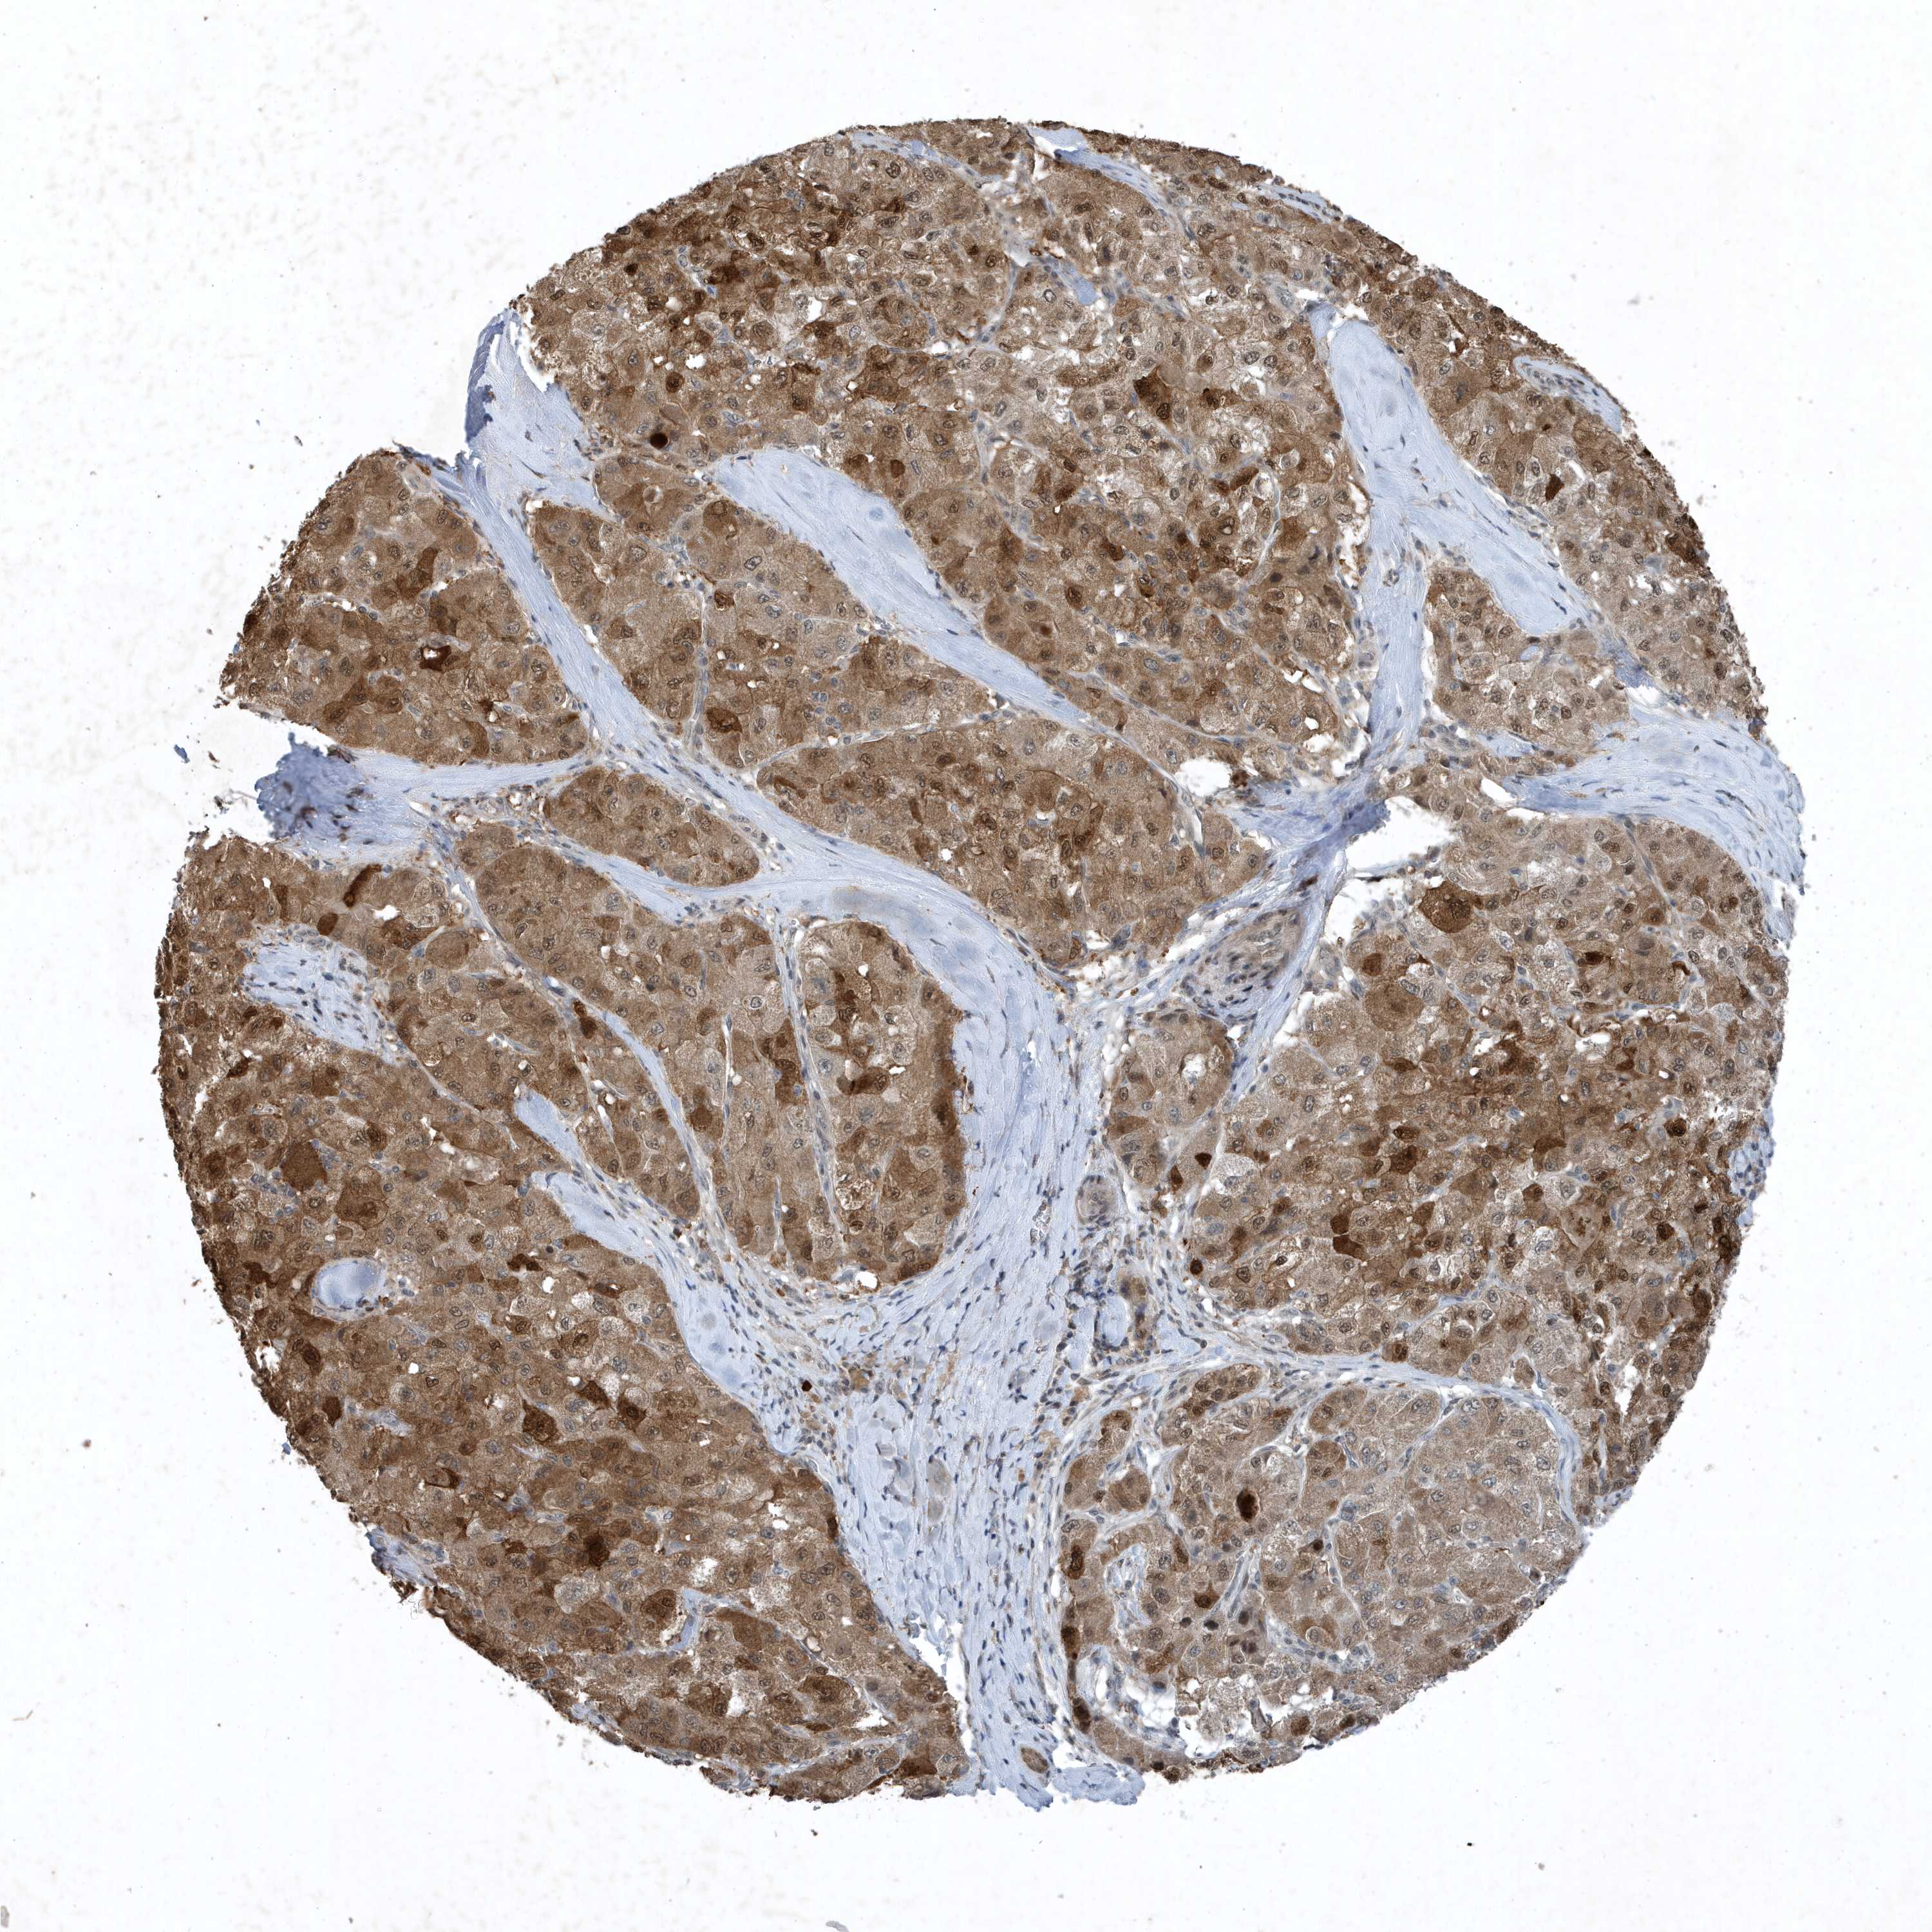

LIVER CANCER - Protein expressioni

A mouse-over function shows sample information and annotation data. Click on an image to view it in a full screen mode. Samples can be filtered based on level of antibody staining by selecting one or several of the following categories: high, medium, low and not detected. The assay and annotation is described here.

Note that samples used for immunohistochemistry by the Human Protein Atlas do not correspond to samples in the TCGA dataset.

Antibody stainingi

Antibody staining in the annotated cell types in the current human tissue is reported as not detected, low, medium, or high, based on conventional immunohistochemistry profiling in selected tissues. This score is based on the combination of the staining intensity and fraction of stained cells.

Each image is clickable and will lead to virtual microscopy that enables deeper exploration of all samples and also displays staining intensity scores, fraction scores and subcellular localization as well as patient and tissue information for each sample.

Antibody HPA052504

Antibody CAB017451

Antibody CAB032815

Staining

High

Medium

Low

Not detected

Intensity

Strong

Moderate

Weak

Negative

Quantity

>75%

75%-25%

<25%

None

Location

Nuclear

Cytoplasmic/membranous

Cytoplasmic/membranous,nuclear

Cholangiocarcinoma

Carcinoma, Hepatocellular, NOS